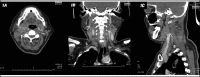

Lemierre's syndrome is characterized by an oropharyngeal infection with internal jugular vein thrombosis followed by metastatic infections in other organs. This infection is usually caused by Fusobacterium spp. In this report, we present a rare case of Klebsiella pneumoniae-associated Lemierre's syndrome in a patient with poorly-controlled diabetes mellitus. The infection was complicated by septic emboli in many organs, which led to the patient's death, despite combined antibiotics, anticoagulant therapy, and surgical intervention. Therein, a literature review was performed for reported cases of Lemierre's syndrome caused by Klebsiella pneumoniae and the results are summarized here.